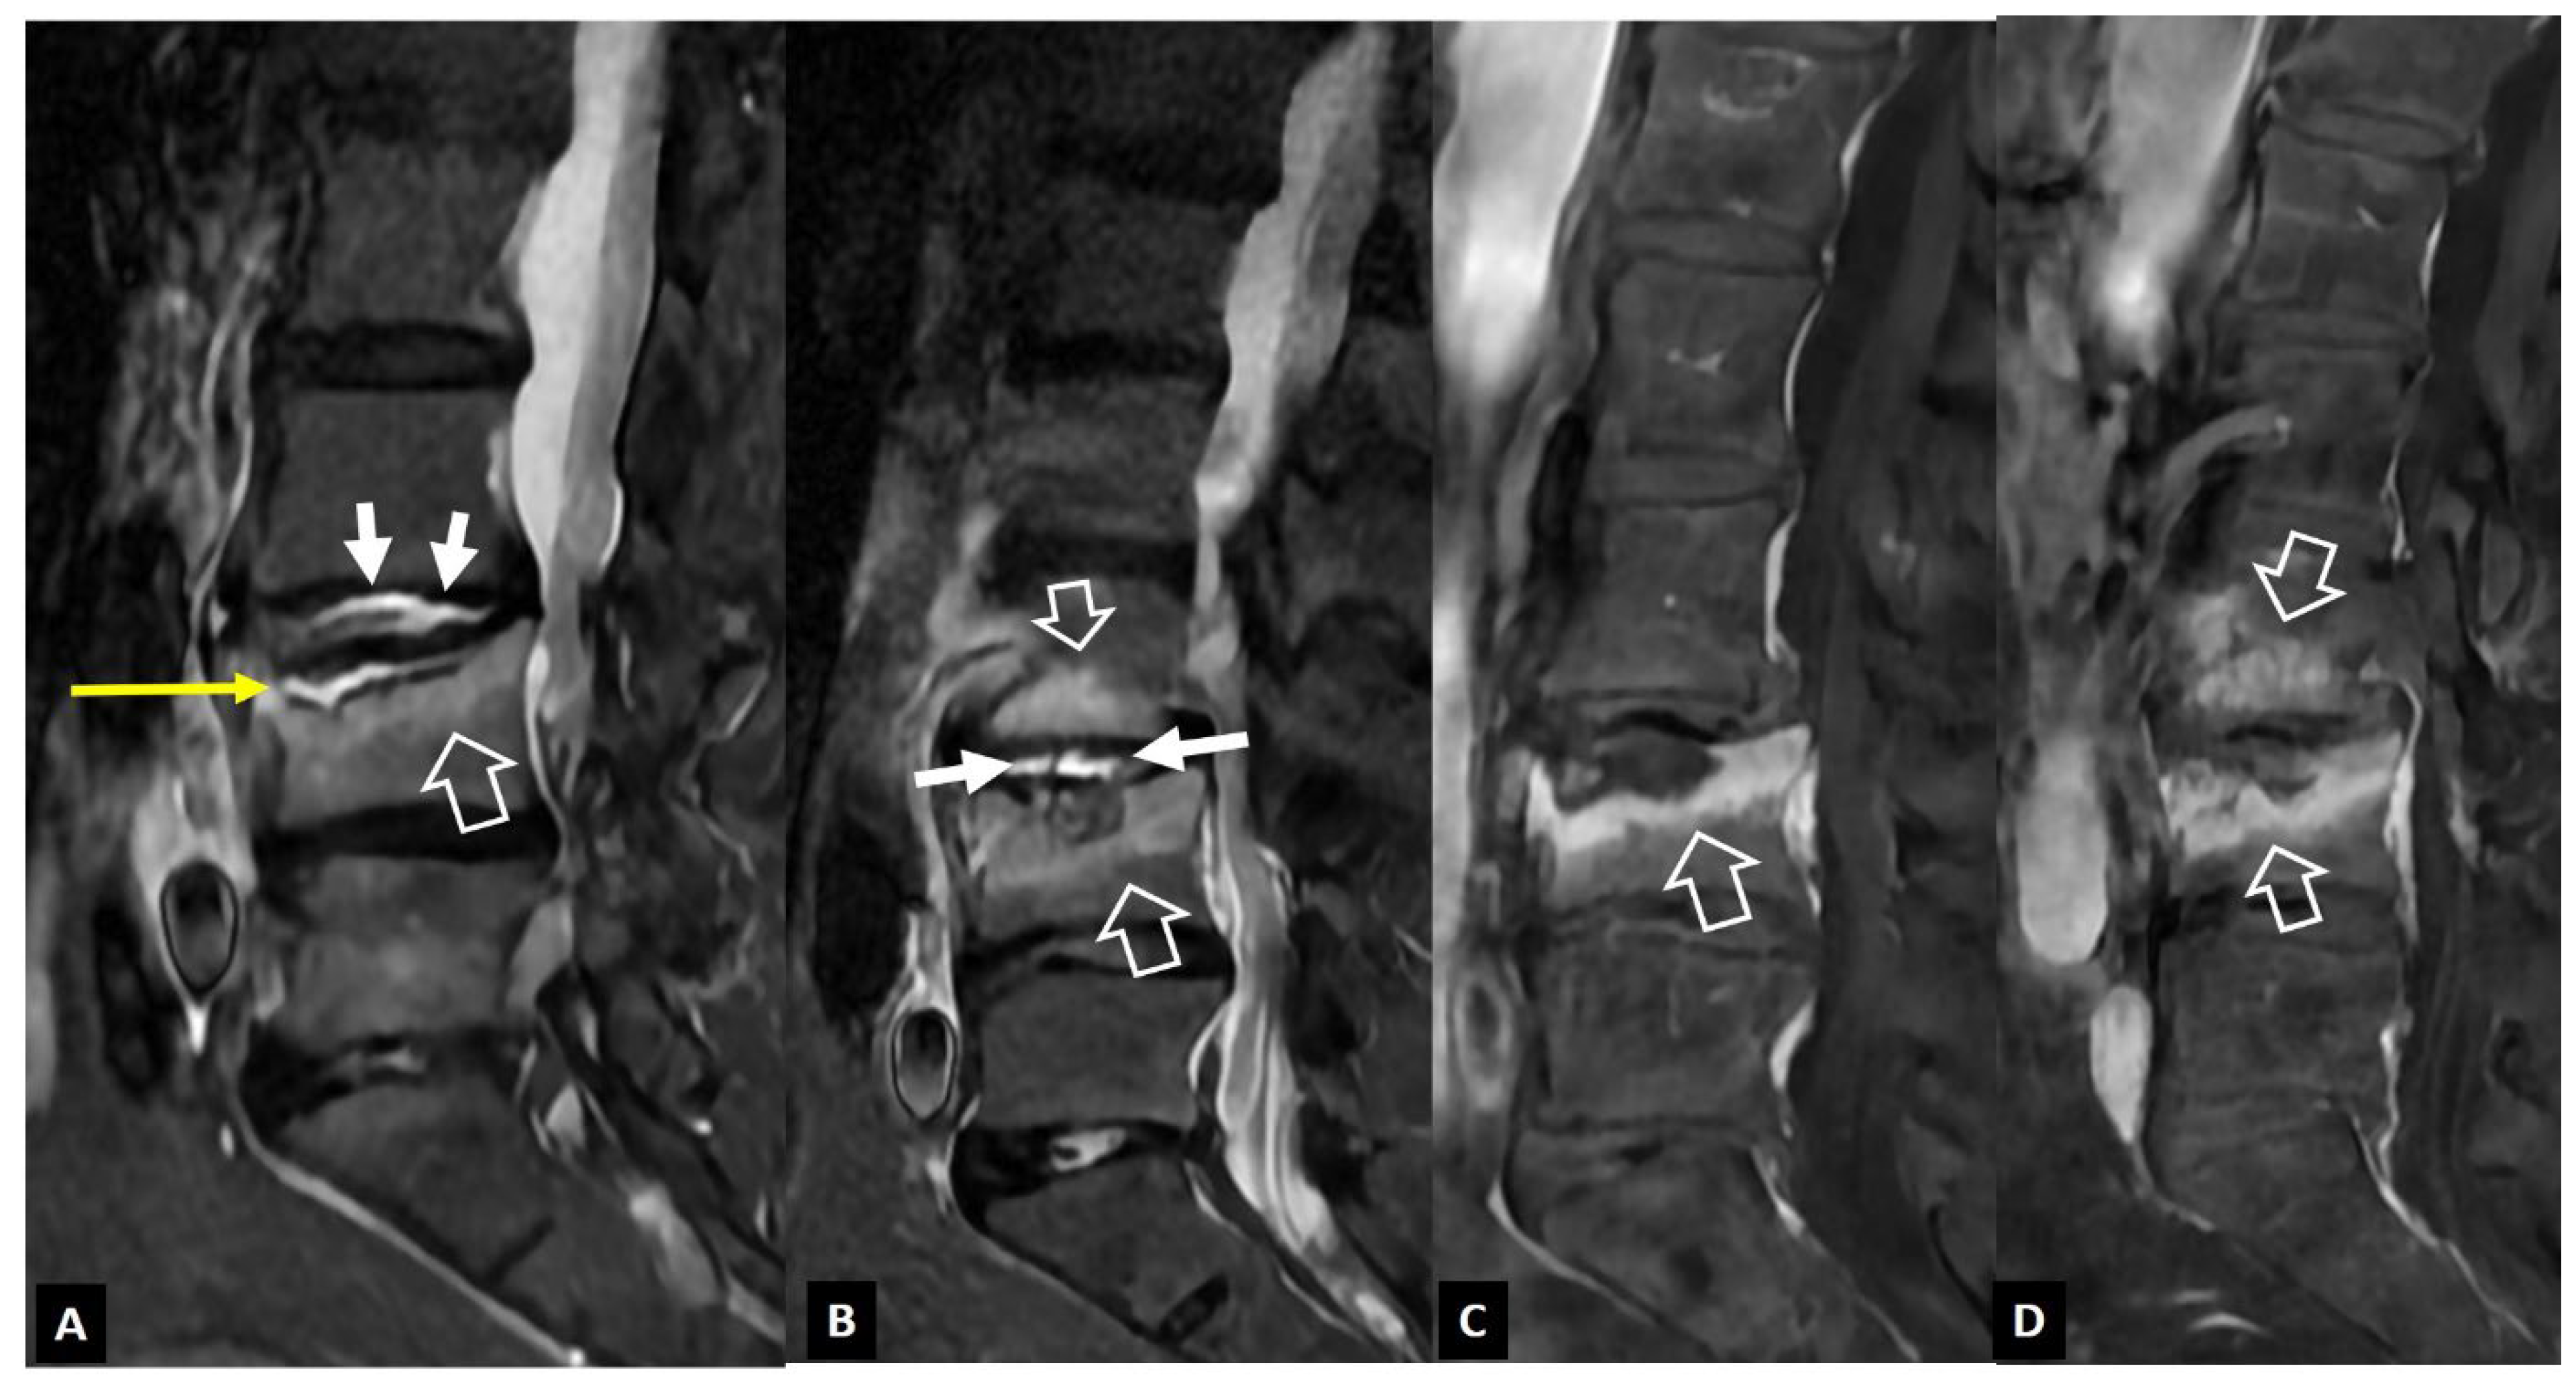

1. a.v. Crystal Deposition

1. a.vi. Postop Aseptic Discitis

1. a.vii. Trauma